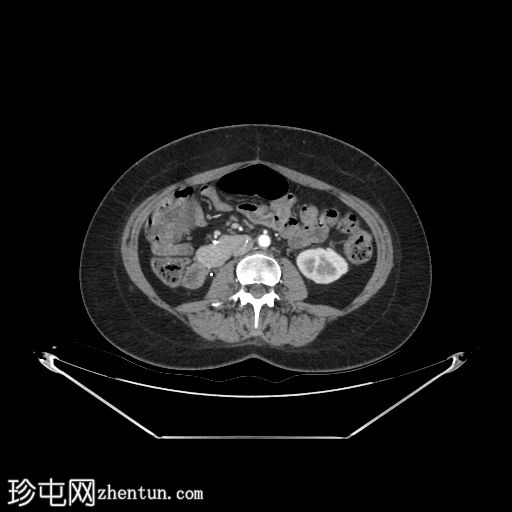

轴位增强扫描

动脉期

移植的胰腺位于右侧腹膜后间隙,大小和形态(轴位、冠状位和矢状位)均正常,可见相关手术缝合线。供体十二指肠段与自体十二指肠吻合。可见胰腺移植物与右髂血管的动脉吻合,胰腺实质强化均匀,提示移植物灌注良好。

本例中,影像学检查显示原位肾脏和胰腺明显萎缩,符合长期糖尿病合并慢性肾脏病的表现。肾移植位于左髂窝,与同侧髂血管的动脉和静脉吻合通畅,肾实质均匀强化,这些影像学表现均符合功能性肾移植的影像学特征。移植胰腺位于右侧腹膜后,形态和位置均符合原位胰腺,供体十二指肠袢与原位十二指肠吻合良好。